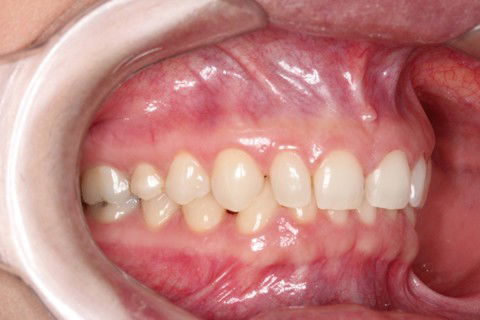

Inicial

Paciente do sexo feminino, 29 anos.

Queixa principal: Espaços generalizados entre os dentes superiores (Diastemas), na qual a paciente relatava apresentar uma aparência infantil. Foi diagnosticado dentes com discrepância negativa de forma e tamanho, mas bem posicionados na arcada. Não sendo indicado fechamento de espaço através aparatologia ortodôntica.

Sugestão de Tratamento: 10 Laminados cerâmicos (Lentes de Contato Dentais), no arco superior contemplando os elementos dentários 15,14,13,12,11,21,22,23,24 e 25.